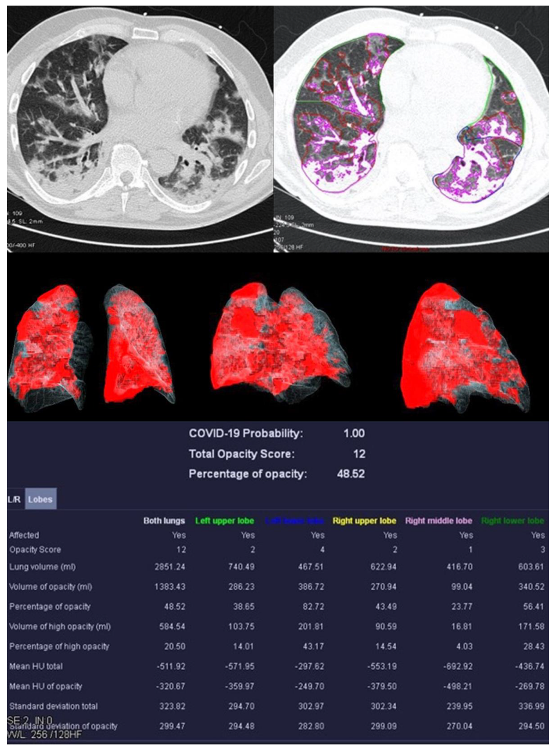

Figure 3.

Examination results of a 61-year-old patient with a severe course of COVID-19 pneumonia. Incipiently consolidating ground glass opacities and sharply defined ground glass opacities with reticulations and crazy-paving patterns.